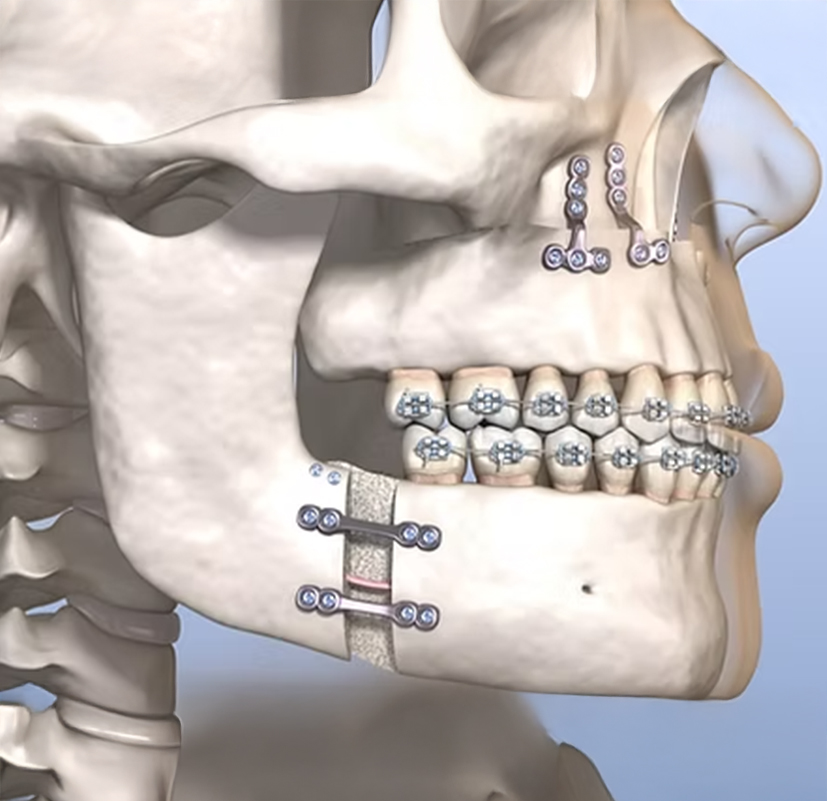

Uzman diş hekimleri; çene hizasızlığı, maloklüzyon (dişlerin yanlış kapanışı) ve iskeletsel bozukluklar gibi sorunları düzeltmek amacıyla modern ve gelişmiş cerrahi teknikler kullanır. Her hasta için detaylı bir değerlendirme yapılarak, ihtiyaç ve beklentilere uygun kişiye özel bir tedavi planı oluşturulur.

Ortognatik cerrahi (cerrahi ortodonti) prosedürü tipik olarak birkaç adım içerir:

Çeneyi yeniden konumlandırma:

Cerrahınız herhangi bir yanlış hizalamayı düzeltmek için çene kemiklerinizi yeniden konumlandıracaktır. Kemikler vidalar veya plakalar kullanılarak yerine sabitlenebilir.